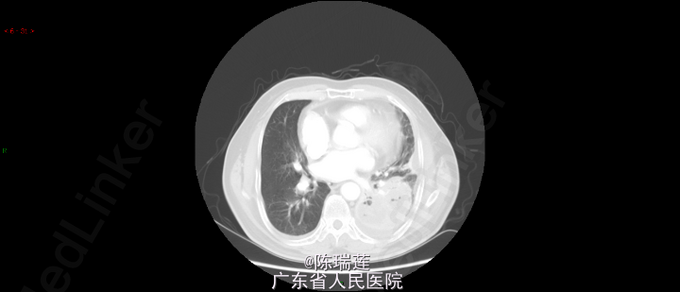

查体:左下肺呼吸音减弱,双侧未闻及干湿啰音。全身浅表淋巴结触及肿大。心律齐,各瓣膜区未闻及杂音。腹部软,无压痛及反跳痛。 查胸部CT示:左肺下叶巨大分叶软组织肿块(78mm*74mm*98mm),注意周围型肺癌可能,肺气肿。

诊断:左下肺鳞癌 行支气管镜检查并活检,活检后病理提示:鳞癌。 因患者住院期间出现发热,予抗感染并止血、止痛、解痉、化痰对症治疗。感染控制后,择期行化疗。

应注意肺部巨大鳞癌时是否有合并空洞的可能性,临床上有些癌性空洞是容易侵犯支气管的血管,从而引起大咯血,危及生命。所以在看到巨大的肿瘤及其治疗时,都应该注意其空洞情况。